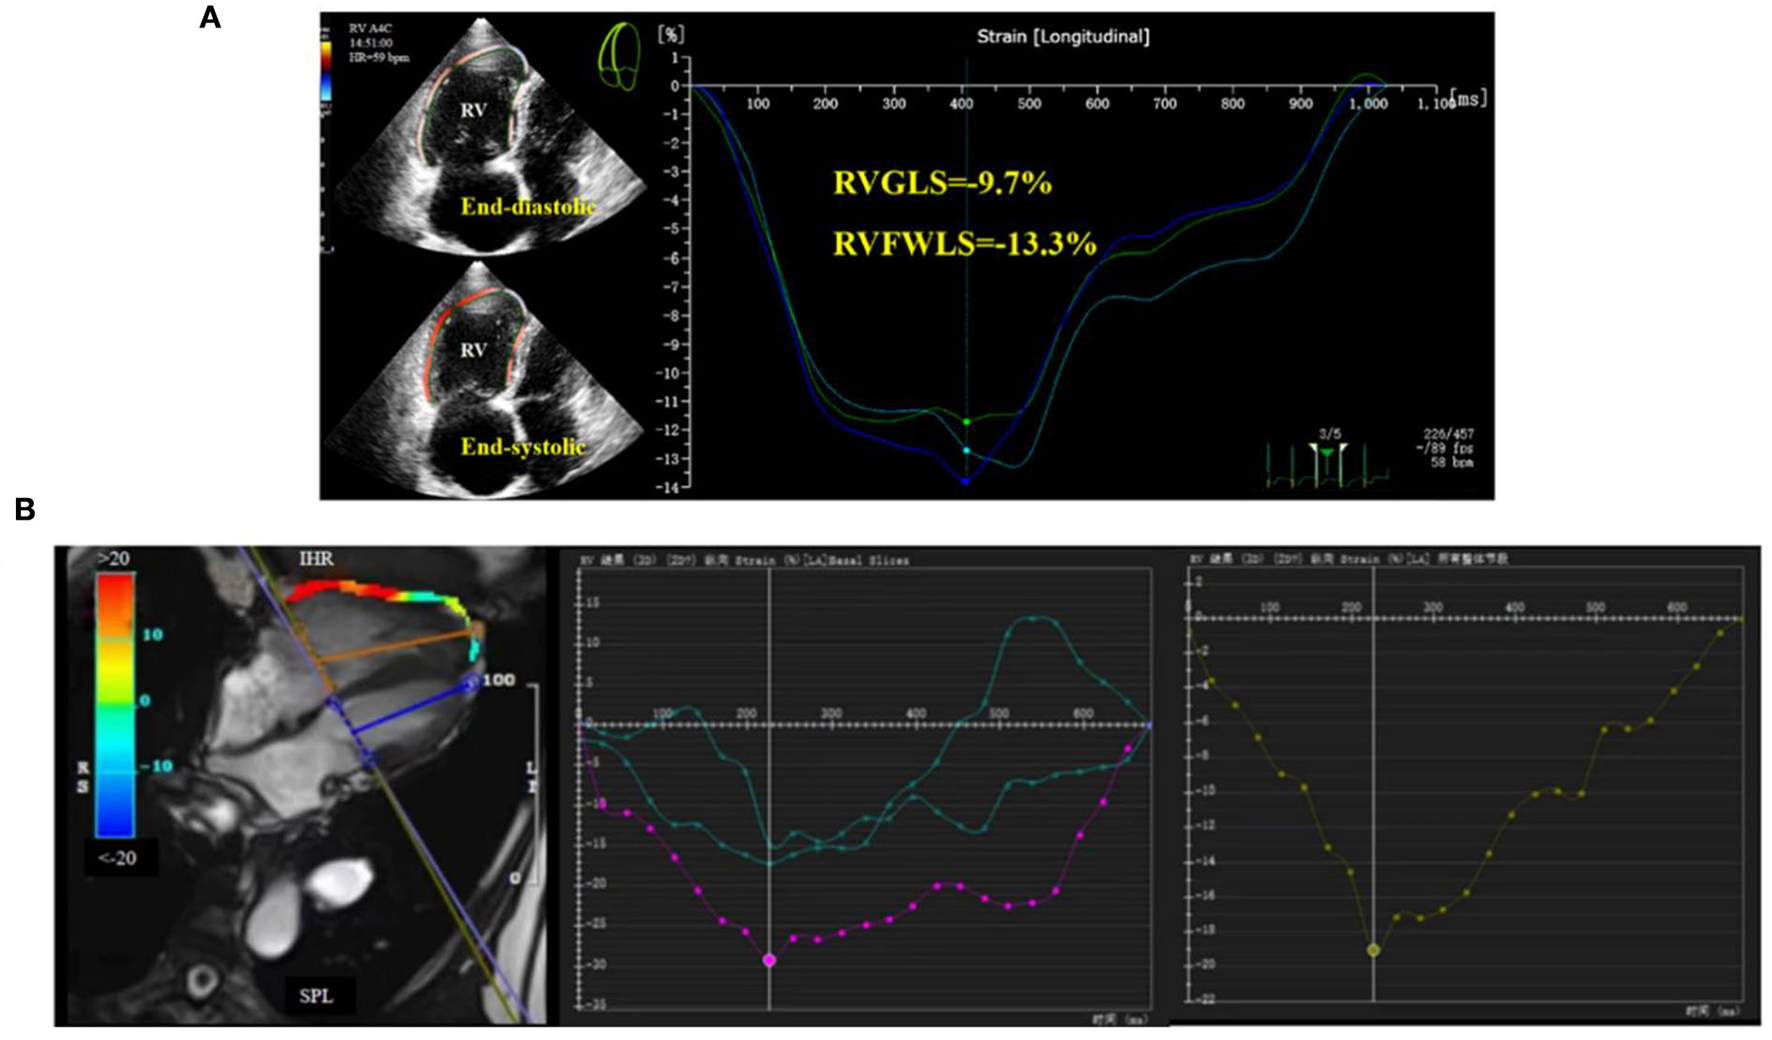

Subsequently, we further divided the study population into two cohorts according to WHO FC: WHO I/II and WHO III. Only CMR-GLS was found to differ significantly between the two groups. Due to the lack of clinical data for some patients, no significant differences were detected for most parameters, but the overall trends for numerical changes were as expected (data not shown). An example of RV strain measurement using post-processing of 2D-STE and CMR-FT images of a CTEPH patient is presented in Figure 1.

Figure 1. Right ventricular global longitudinal strain (RVGLS) determination in CTEPH patients. (A) 2D-STE for measurement of RVGLS, and (B) CMR-FT for measurement of RVGLS.